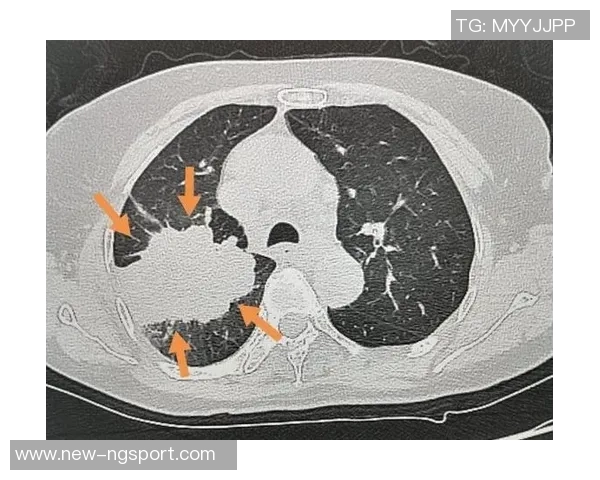

除了常规医疗措施外,医院还采用了一些新技术,比如心电图监测和超声波检查,这些手段帮助医生及时掌握卡洛斯的病情变化。同时,通过详细记录患者的信息与数据,为今后的复查提供重要参考。这种严谨且系统化的方法,大大提高了治疗效率。